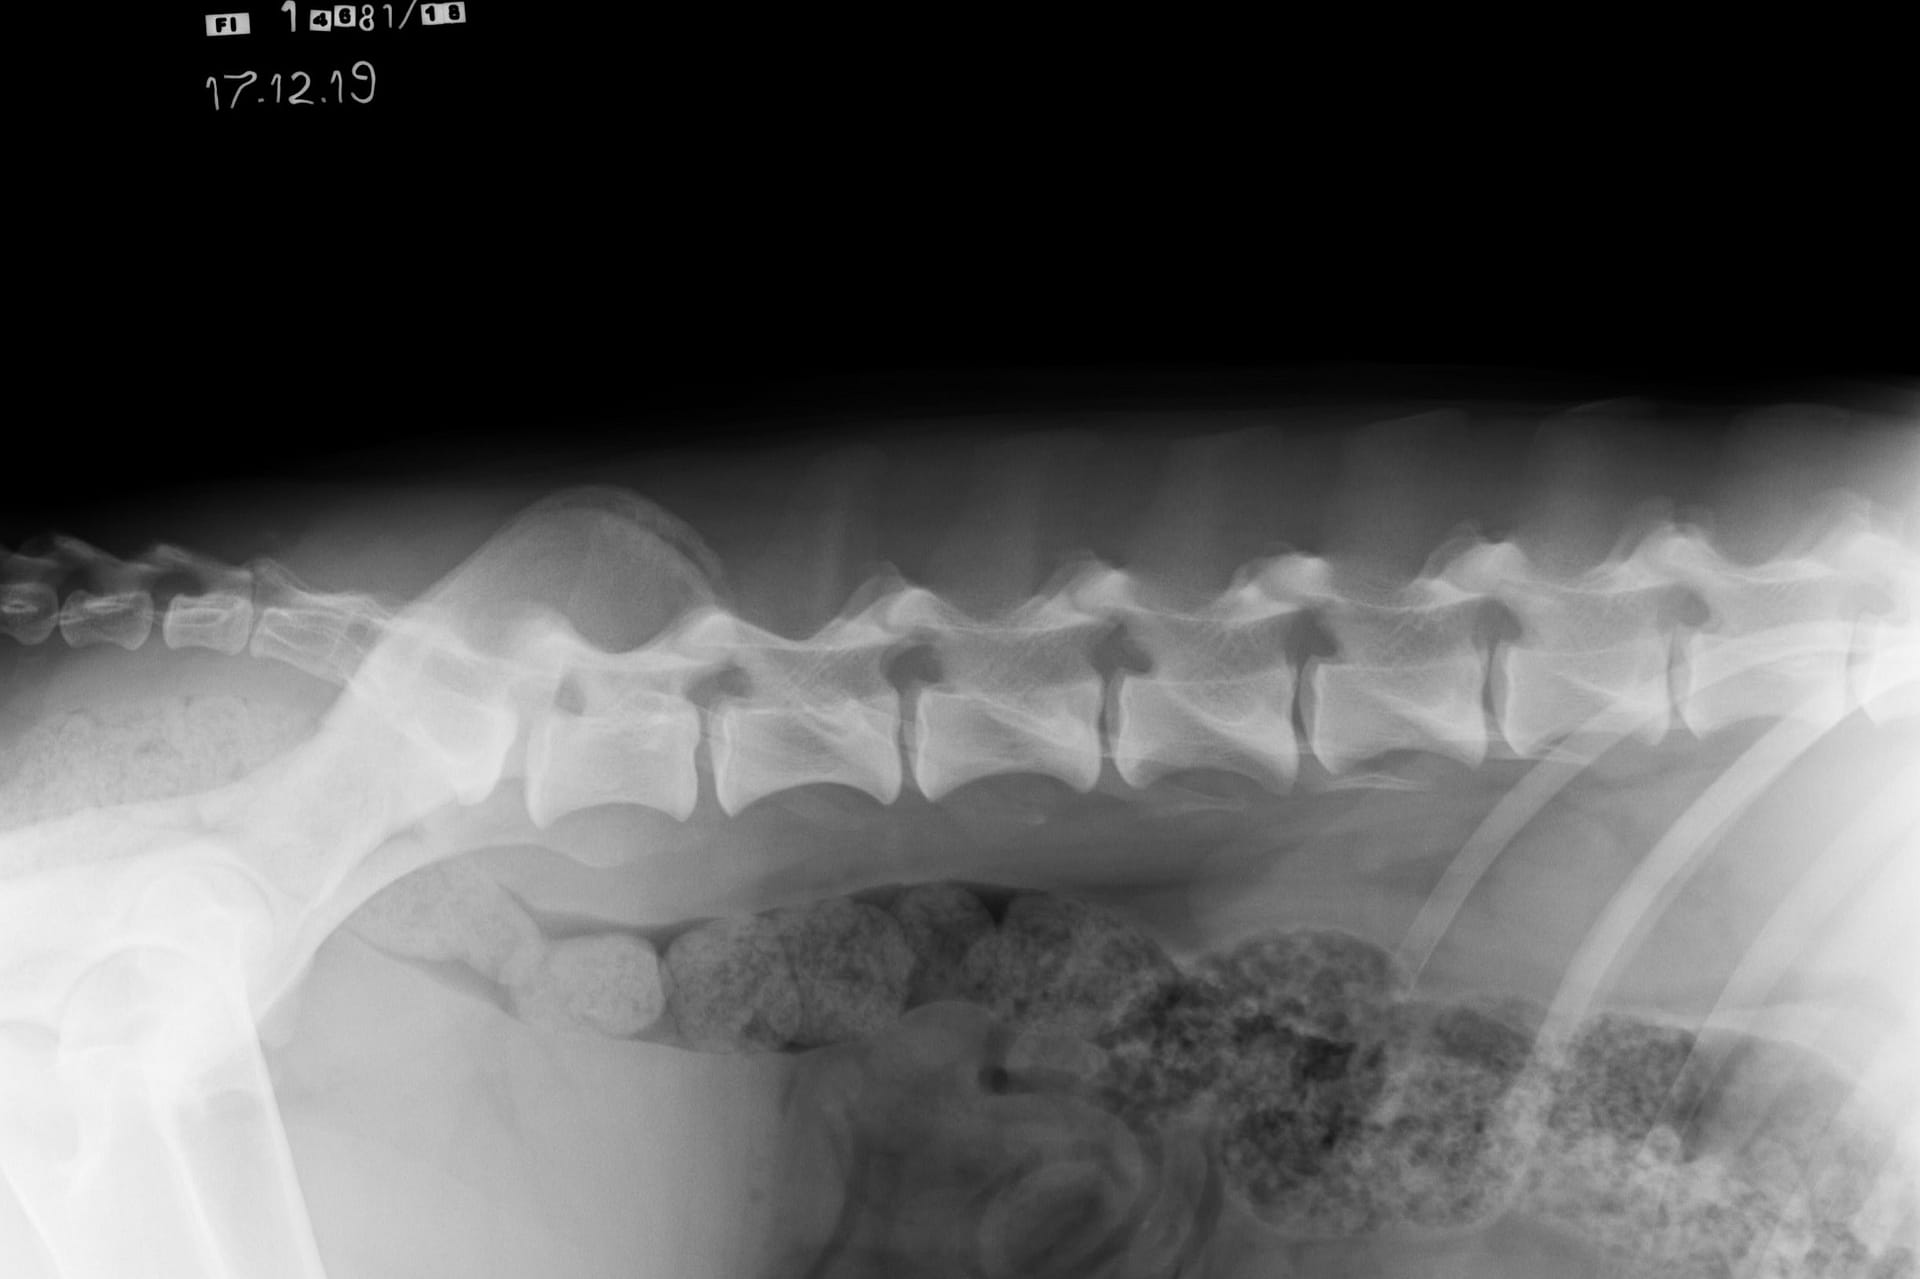

By radiographing the cervical spine, thoracic spine, lumbar spine and sacrum it’s possible to get grading for the LTV, spondylosis (SP) and vertabral anomaly (VA). In Finland for the LTV and VA scoring the must be at least 12 months old and 24 months old for the spondylosis. Instructions for radiography: https://www.kennelliitto.fi/en/forms/idd-ltv-and-spondylosis-instructions-radiography

normal spine

A normal canine spine consists of 7 cervical (C1-7), 13 thoracic (T1-13), 7 lumbar (L1-7) and 3 sacral vertebras (S1-3) resulting the total of 30 vertebras. Calculation starts from first thoracic vertebra (T1). The number of caudal vertebras (CD) vary.